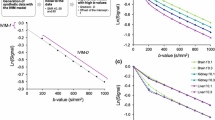

DCE-MRI data processing was performed off-line using MRIW software (The Institute of Cancer Research, London, UK), using the same slices and ROIs as for the DW-MRI. The proton-density weighted images acquired post-contrast were used with the dynamically acquired T1-weighted images to generate contrast agent concentrations on a per-voxel basis [18, 19]. Relaxivities of Magnevist® and Dotarem® at 1.5 T were taken to be 4.3 and 4.2 mM-1 sec-1, respectively. The model-independent parameters evaluated were: (i) IAUGC60, in mM.sec, and (ii) the pre-contrast T1, in seconds. Pharmacokinetic model analysis was performed using an extended Tofts model and a population-averaged arterial input function (AIF), measured from a subset of the study cohort where a suitable ROI could be drawn along the descending aorta on or near the central partition (Fig. 1a). Dynamic signal intensities averaged over the ROI were converted to contrast agent concentrations as for the lesion data, and an empirical input function model consisting of components describing the first pass, second pass, and equilibrium phases was fitted to the data [20, 21]:

where C B (t) models dispersion in the lungs, C R (t) describes the recirculation phase with a delay t R , and both are modelled with raised cosine functions [22]. R M (t) is an impulse response modelling the mixing through the heart, given by R M (t) = α M exp(−μ M t) , and R E (t) is an impulse response modelling reflux of contrast from the whole-body extra-vascular space: R E (t) = α E exp(−μ E t). The input function is thus defined by eight parameters: aB, μB, μM (first pass phase), aR, μR, tR (second pass phase), aE and μE (equilibrium phase). A population-averaged paediatric AIF was constructed by taking the median of the individual AIF parameters after accounting for variations in haematocrit measured in individual patients. The DCE-MRI model-dependent parameters evaluated were: (i) Ktrans, in min-1, (ii) kep, in min-1, (iii) ve, and (iv) vp.

(a) T1-weighted DCE-MR image at peak arterial enhancement in the descending aorta with a region-of-interest (turquoise) used for measurement of arterial input function overlaid. (b) Population-averaged input functions obtained from a subset of children in this study cohort (red) and from adult patients (blue) [20] fitted to an empirical input function model C. The input function parameters are summarised in Table 1. Only the first two minutes of the concentration-time course data have been shown for display purposes

Nine study-specific, individual AIFs were obtained from DCE-MRI. The cohort-averaged paediatric AIF is shown in Fig. 1b together with an adult population-averaged AIF refitted to the input function model in Eq. 1 [20, 23] with an assumed haematocrit of 0.42. First-pass and recirculation peaks were found to be sharper and to occur earlier in the paediatric AIF; parameters for the two population-averaged AIFs are given in Table 2.

For DCE-MRI measurements, we employed a 3-D volumetric protocol with good spatial and temporal resolutions. The dynamic temporal resolution employed (~3 s) not only helped to minimise motion artefacts but also helped to capture the contrast uptake curves in the tumour and the descending aorta (where signal changes occur rapidly). Using the contrast uptake curves from the descending aorta, it was possible to construct a paediatric population AIF (Fig. 1b), observed to have features distinct from those seen in an adult population [23] and consistent with the relatively high rate of circulation seen in children. Although limited patient numbers preclude investigation of AIF variations with age in this present study, the differences observed between the paediatric and adult population AIFs highlight the importance of conducting such investigations in the future. Additionally, it is important to optimise the injection protocol in patients with an implanted central venous line to minimise the variability observed with hand injections [20].